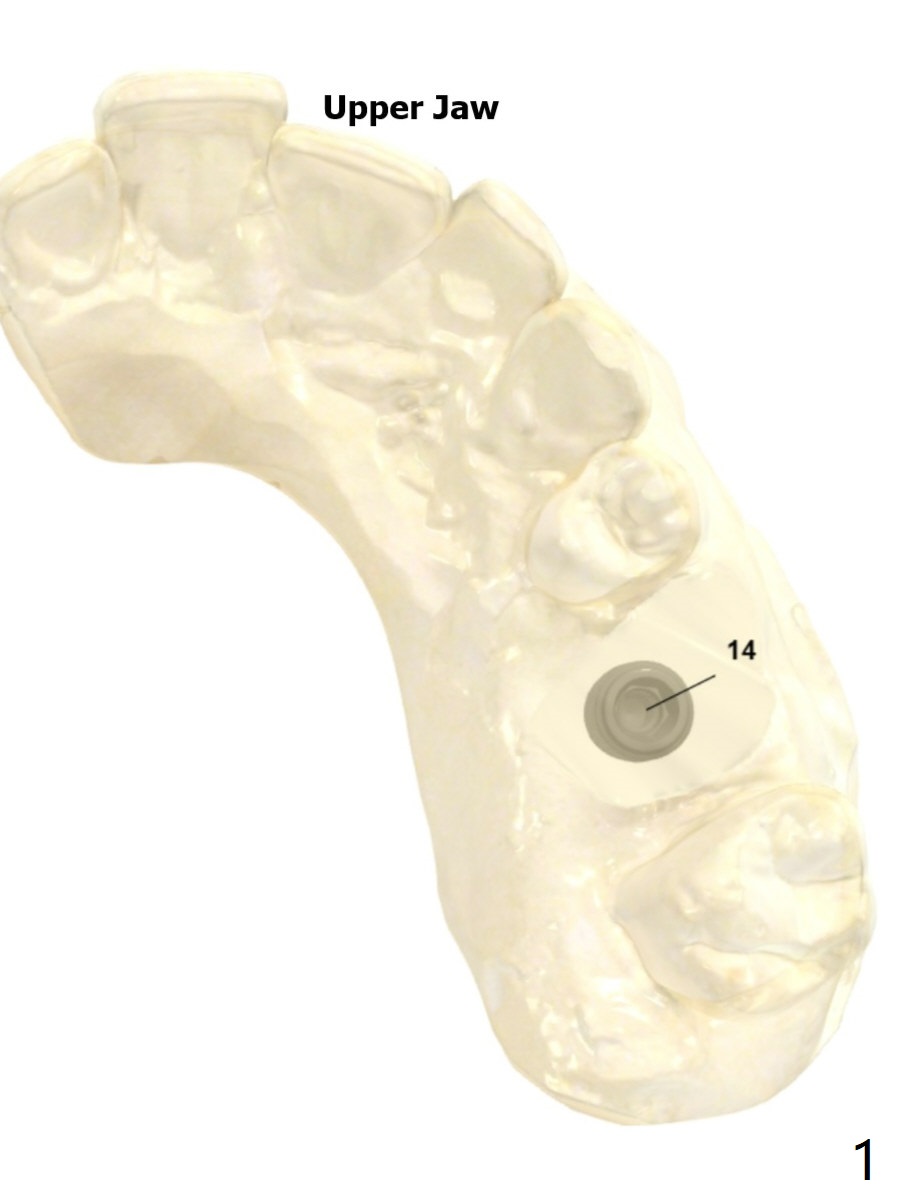

Upper Molar Immediate Implant Shield Trajectory II Shield Xin Wei, DDS, PhD, MS 1st edition 10/30/2019, last revision 02/21/2021